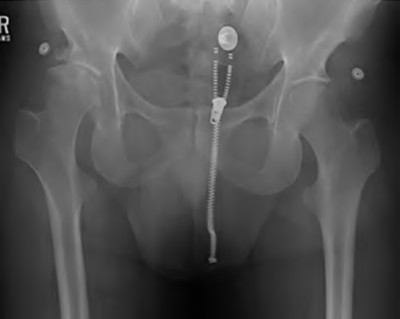

Question 97

Which of the following prophylactic regimens is considered most effective for a patient with a prior history of severe heterotopic ossification undergoing a revision total hip arthroplasty?

Explanation